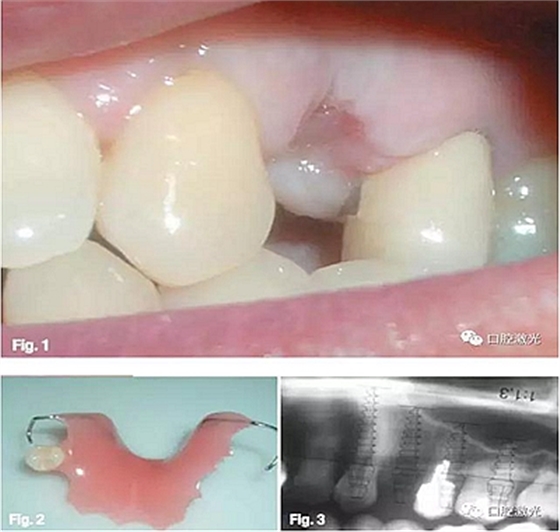

患者32歲女性,24根折后佩戴活動(dòng)義齒。六周后,由于感到生活不便,希望安裝固定義齒。通過口腔檢查發(fā)現(xiàn),23和25均存在不適合安裝固定義齒的情況,但符合種植牙的基本條件,遂選擇進(jìn)行口腔種植。

臨床步驟